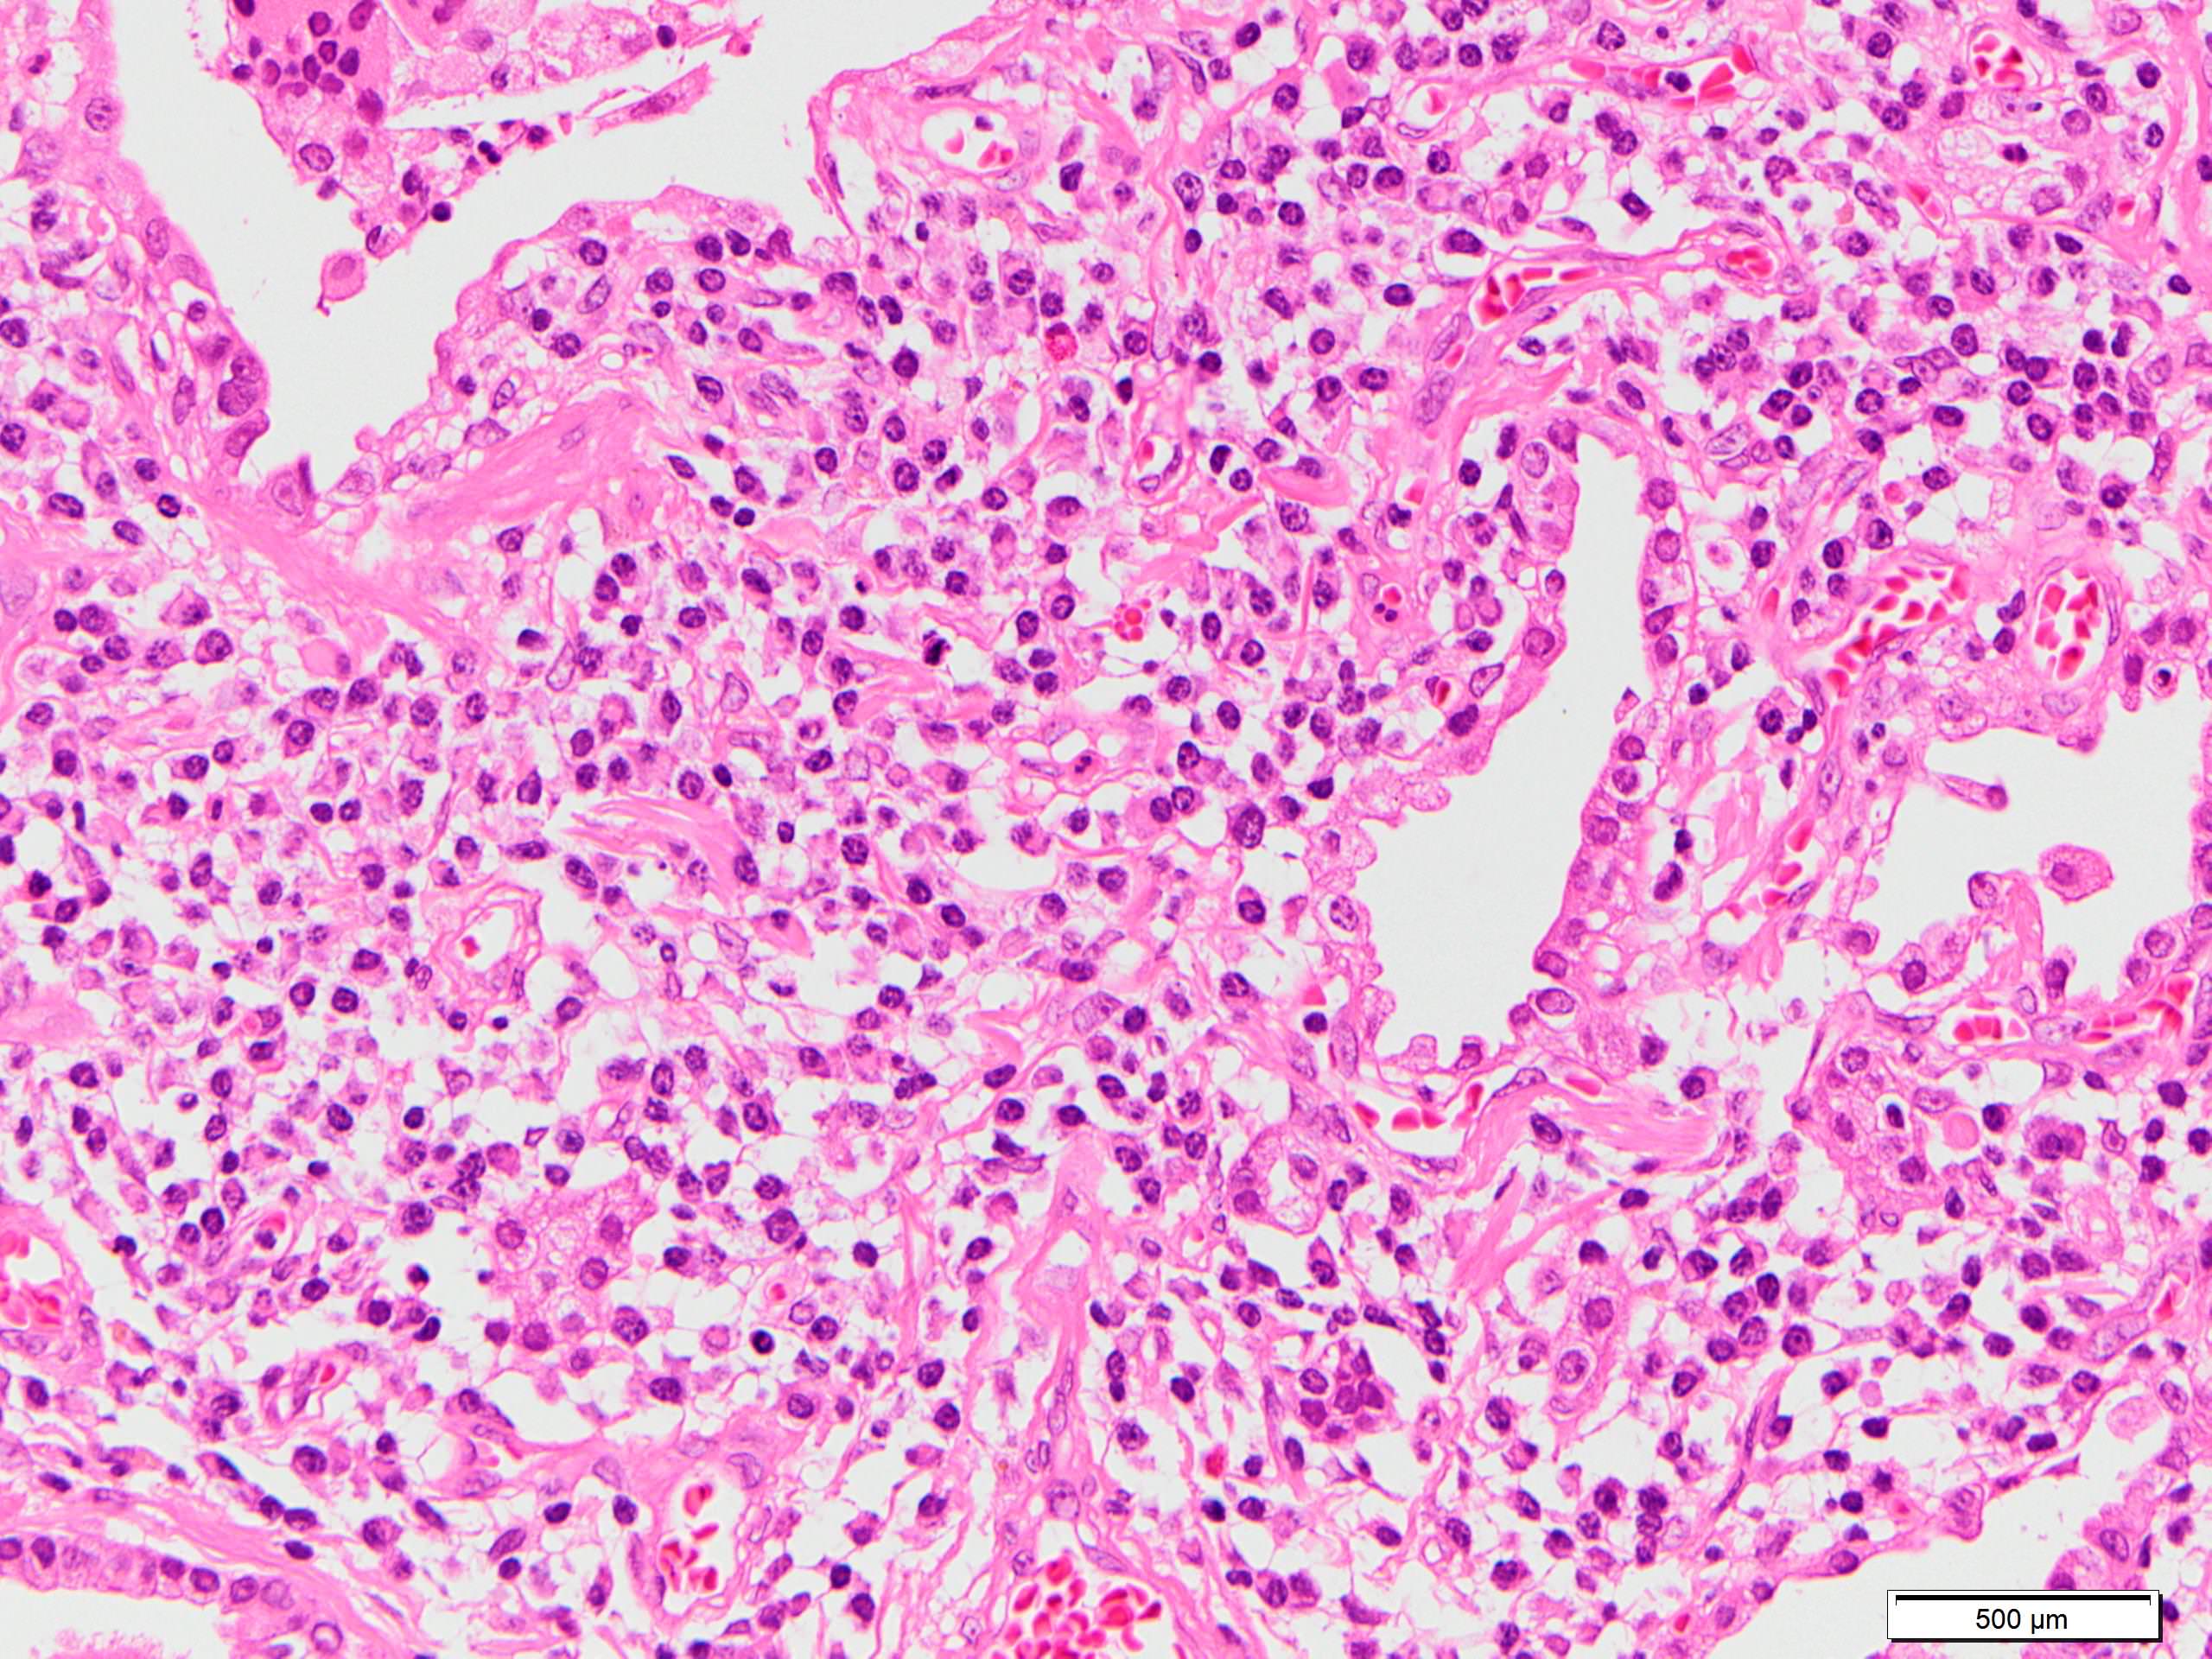

Microscopic (histologic) description

- Since there are few specific findings for NSIP pattern, it is essential to exclude other lung diseases on histology (Am J Respir Crit Care Med 2008;177:1338)

- Characteristic findings of NSIP pattern

- Diffuse and uniform inflammation ("temporal homogeneity") on low power of alveolar wall, bronchovascular bundles and pleura

- Cellular or fibrotic change

- Lymphocytic or plasmacytic infiltration

- Loose fibrosis

- Lung architecture is frequently preserved

Microscopic (histologic) images

Scroll to see all images.

Contributed by Akira Yoshikawa, M.D.